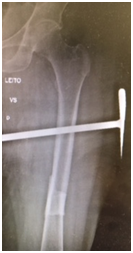

We report a case of bilateral femoral fracture in a patient after 7 years of treatment with alendronate at a dose of 70 mg weekly. The patient was a 67 y.o. female with no history of any comorbidity such as diabetes, alcohol abuse, smoking, chronic use of glucocorticoids or others. She fell from her own height in March 2014, resulting in a transverse femoral shaft fracture of the left femur (Figure 1A), treated with a blocked anterograde intramedullary nail (Figure 1B & 1C). In June 2016, she suffered a contralateral short oblique femoral fracture with no history of direct trauma, presumably with a torsional mechanism - rotation around the body axis (Figure 2A). The treatment of choice was also a blocked anterograde intramedullary nail (Figures 2B & 2C). We can observe in Figures 1 & 2 the absence of compromised trabecular bone or thinning of cortical bone, corroborating the probable pathophysiology behind bisphosphonate-associated fractures - decreased bone remodelling - and not osteopenia/osteoporosis.

Figure 1A Left femoral anteroposterior radiograph - Simple short oblique tract fracture with cortical thickening. 1B & 1C Postoperative radiograph – anterograde blocked nail left femur.